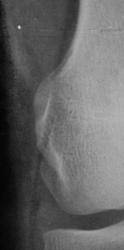

Травма. Пациент направлен на рентгенографию коленного сустава.

Пациент направлен на рентгенографию коленного сустава.

Определяется уплотнение кортикального слоя суставных поверхностей, заострение межмыщелковых возвышении, слабовыраженная краевая  костная деформация - по совокупности   тянет на ДОА I ст. Ну, а то, что на прицельной то это - игра теней - мое мнение.

Прицельных снимков не делали, это обычных два снимка на цифре.

ДФА 1

артроз пателло-феморального суставчика и лигаментоз крестовидных связок.